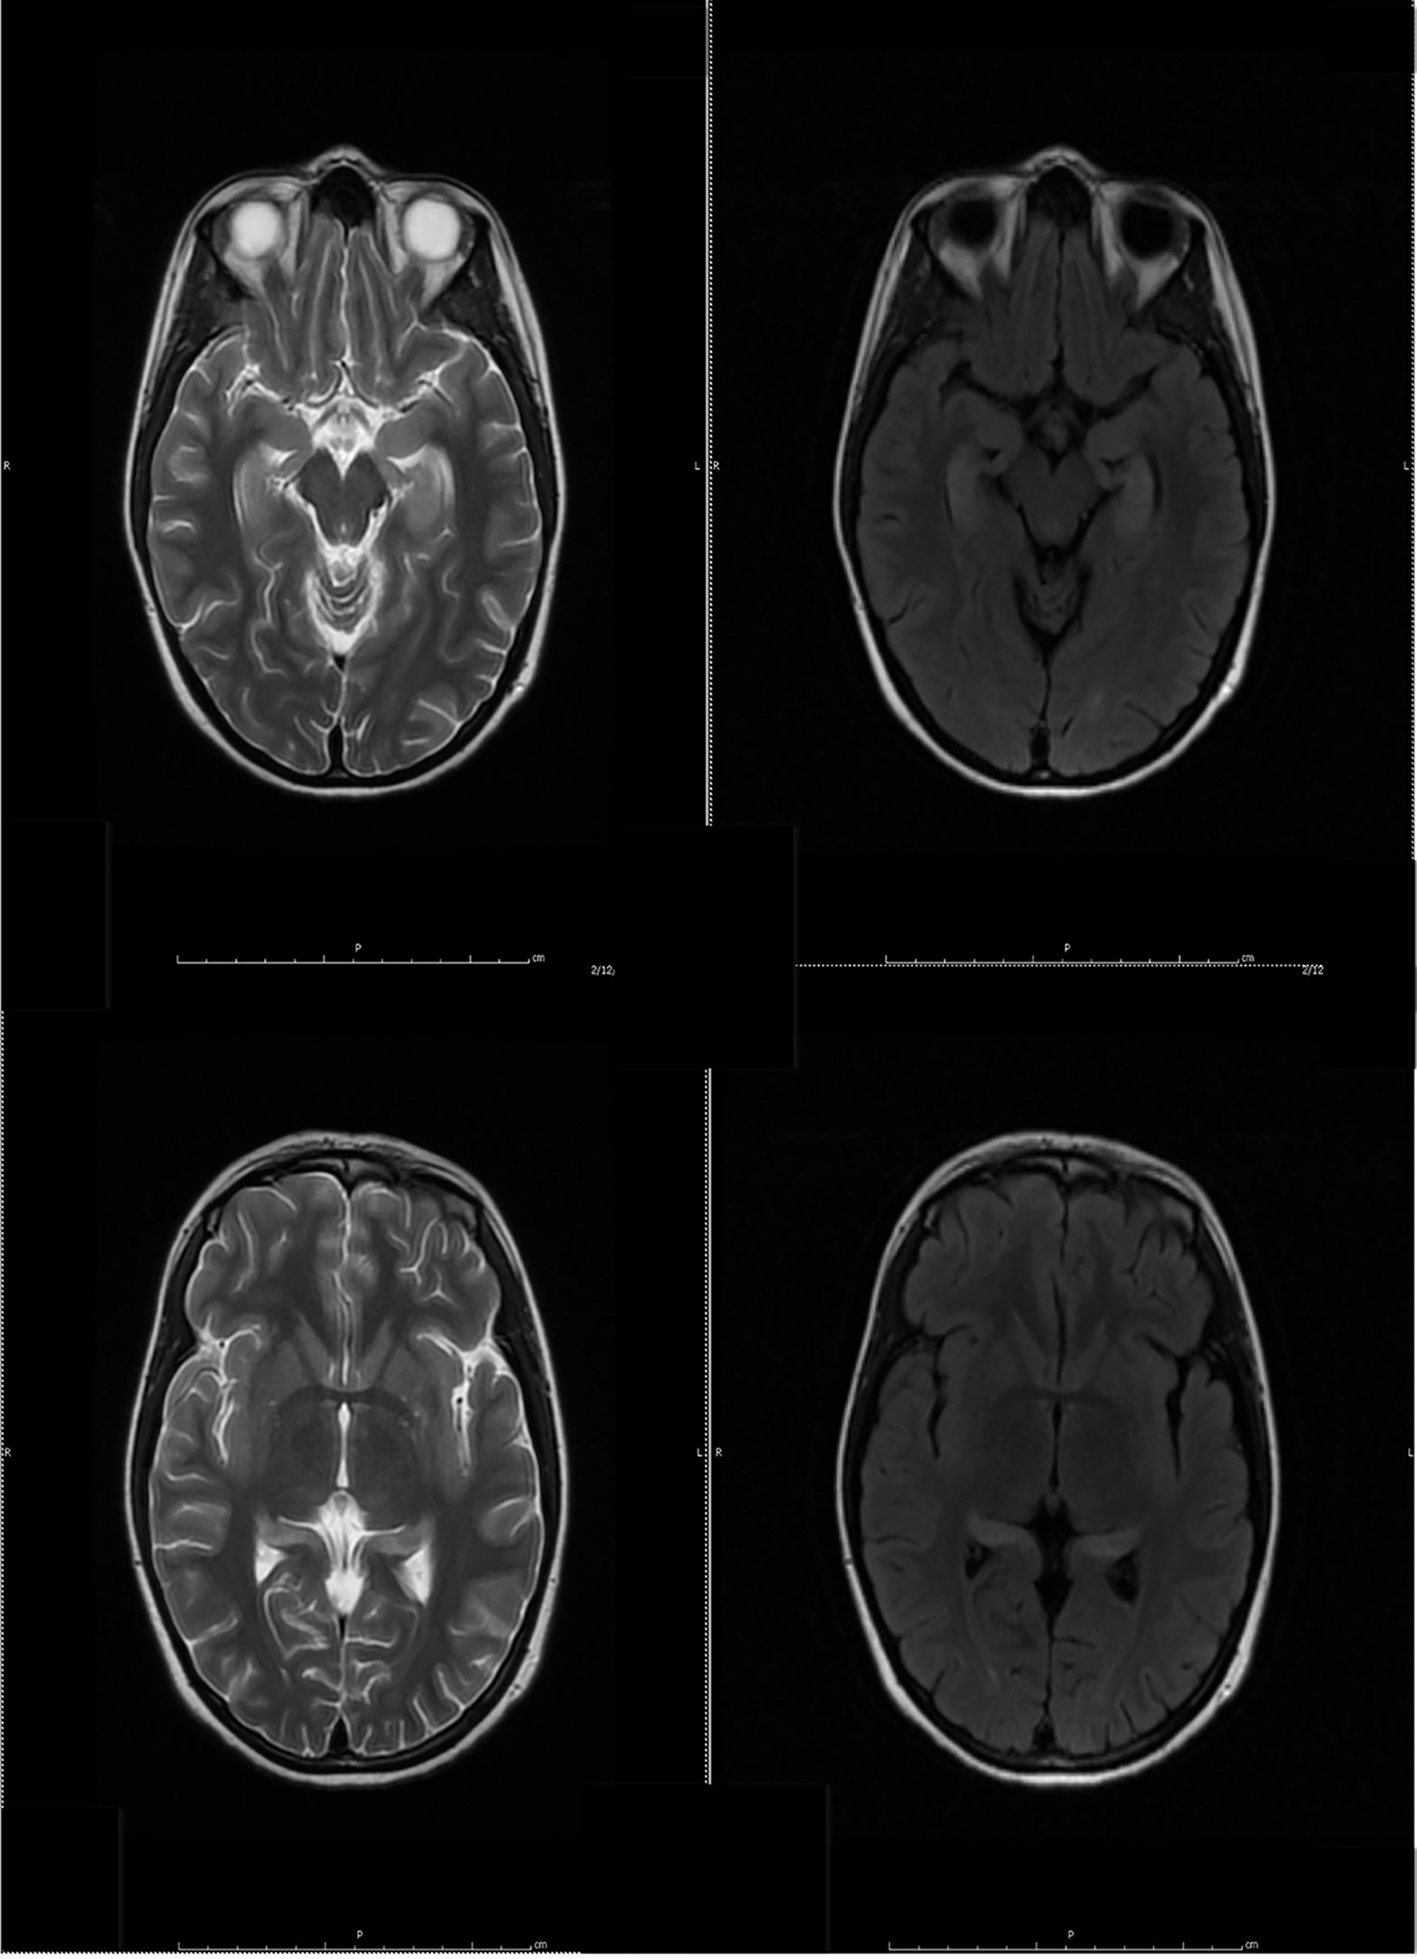

Despite the seizure medicine, the patient’s memory continued to deteriorate. The follow-up MRI of the brain showed significant stepwise interval increase in the extent of T2 signal intensity in the bilateral hippocampus, amygdala, fornix, and mammillary body on fluid-attenuated inversion recovery (FLAIR) sequences (Figs. 2 and 3) [7]. MRI depicted in Figs. 2 and 3 was 1 month apart.

![]() Click for large image | Figure 2. The follow-up MRI of brain showed interval increase in the extent of T2 signal intensity in the bilateral hippocampus, amygdala, fornix and mammillary body on fluid-attenuated inversion recovery (FLAIR) sequences. MRI obtained in Figure 1 and Figure 2 was 1 week apart. |

![]() Click for large image | Figure 3. The follow-up MRI of brain showed significant interval increase in the extent of T2 signal intensity in the bilateral hippocampus, amygdala, fornix and mammillary body on fluid-attenuated inversion recovery (FLAIR) sequences. MRI obtained in Figure 2 and Figure 3 was 1 month apart. |